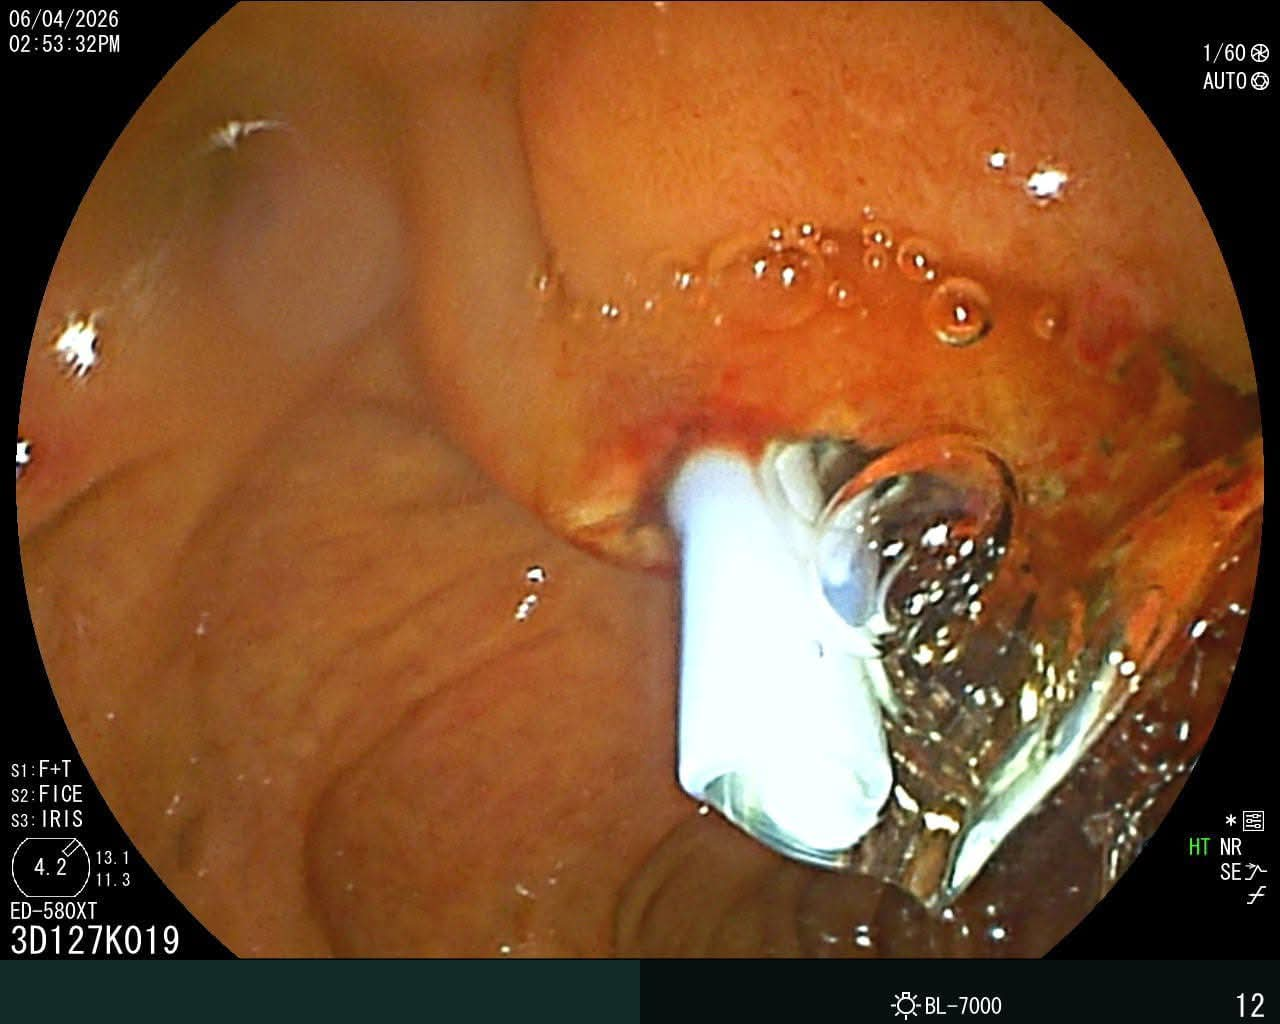

وتمكن الفريق الطبي من إجراء التدخل الدقيق بنجاح، حيث شمل إزالة دعامة من القنوات المرارية، واستخراج حصوة من المرارة، إلى جانب تركيب دعامات جديدة بالقنوات المرارية، بما ساهم في تحسين الحالة الصحية للمريض وتجنب التدخل الجراحي التقليدي.

ويُعد منظار ERCP من الإجراءات الطبية الدقيقة المستخدمة في تشخيص وعلاج أمراض القنوات المرارية والبنكرياس، مثل إزالة الحصوات، وعلاج الانسدادات، وتركيب الدعامات، ما يساهم في تقليل الحاجة إلى العمليات الجراحية، ويُسرّع من وتيرة تعافي المرضى.